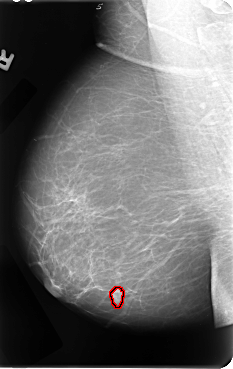

FILE: B_3067_1.RIGHT_MLO.OVERLAY

TOTAL_ABNORMALITIES 1

ABNORMALITY 1

LESION_TYPE MASS SHAPE LOBULATED MARGINS CIRCUMSCRIBED-ILL_DEFINED

ASSESSMENT 4

SUBTLETY 4

PATHOLOGY MALIGNANT

TOTAL_OUTLINES 1

BOUNDARY